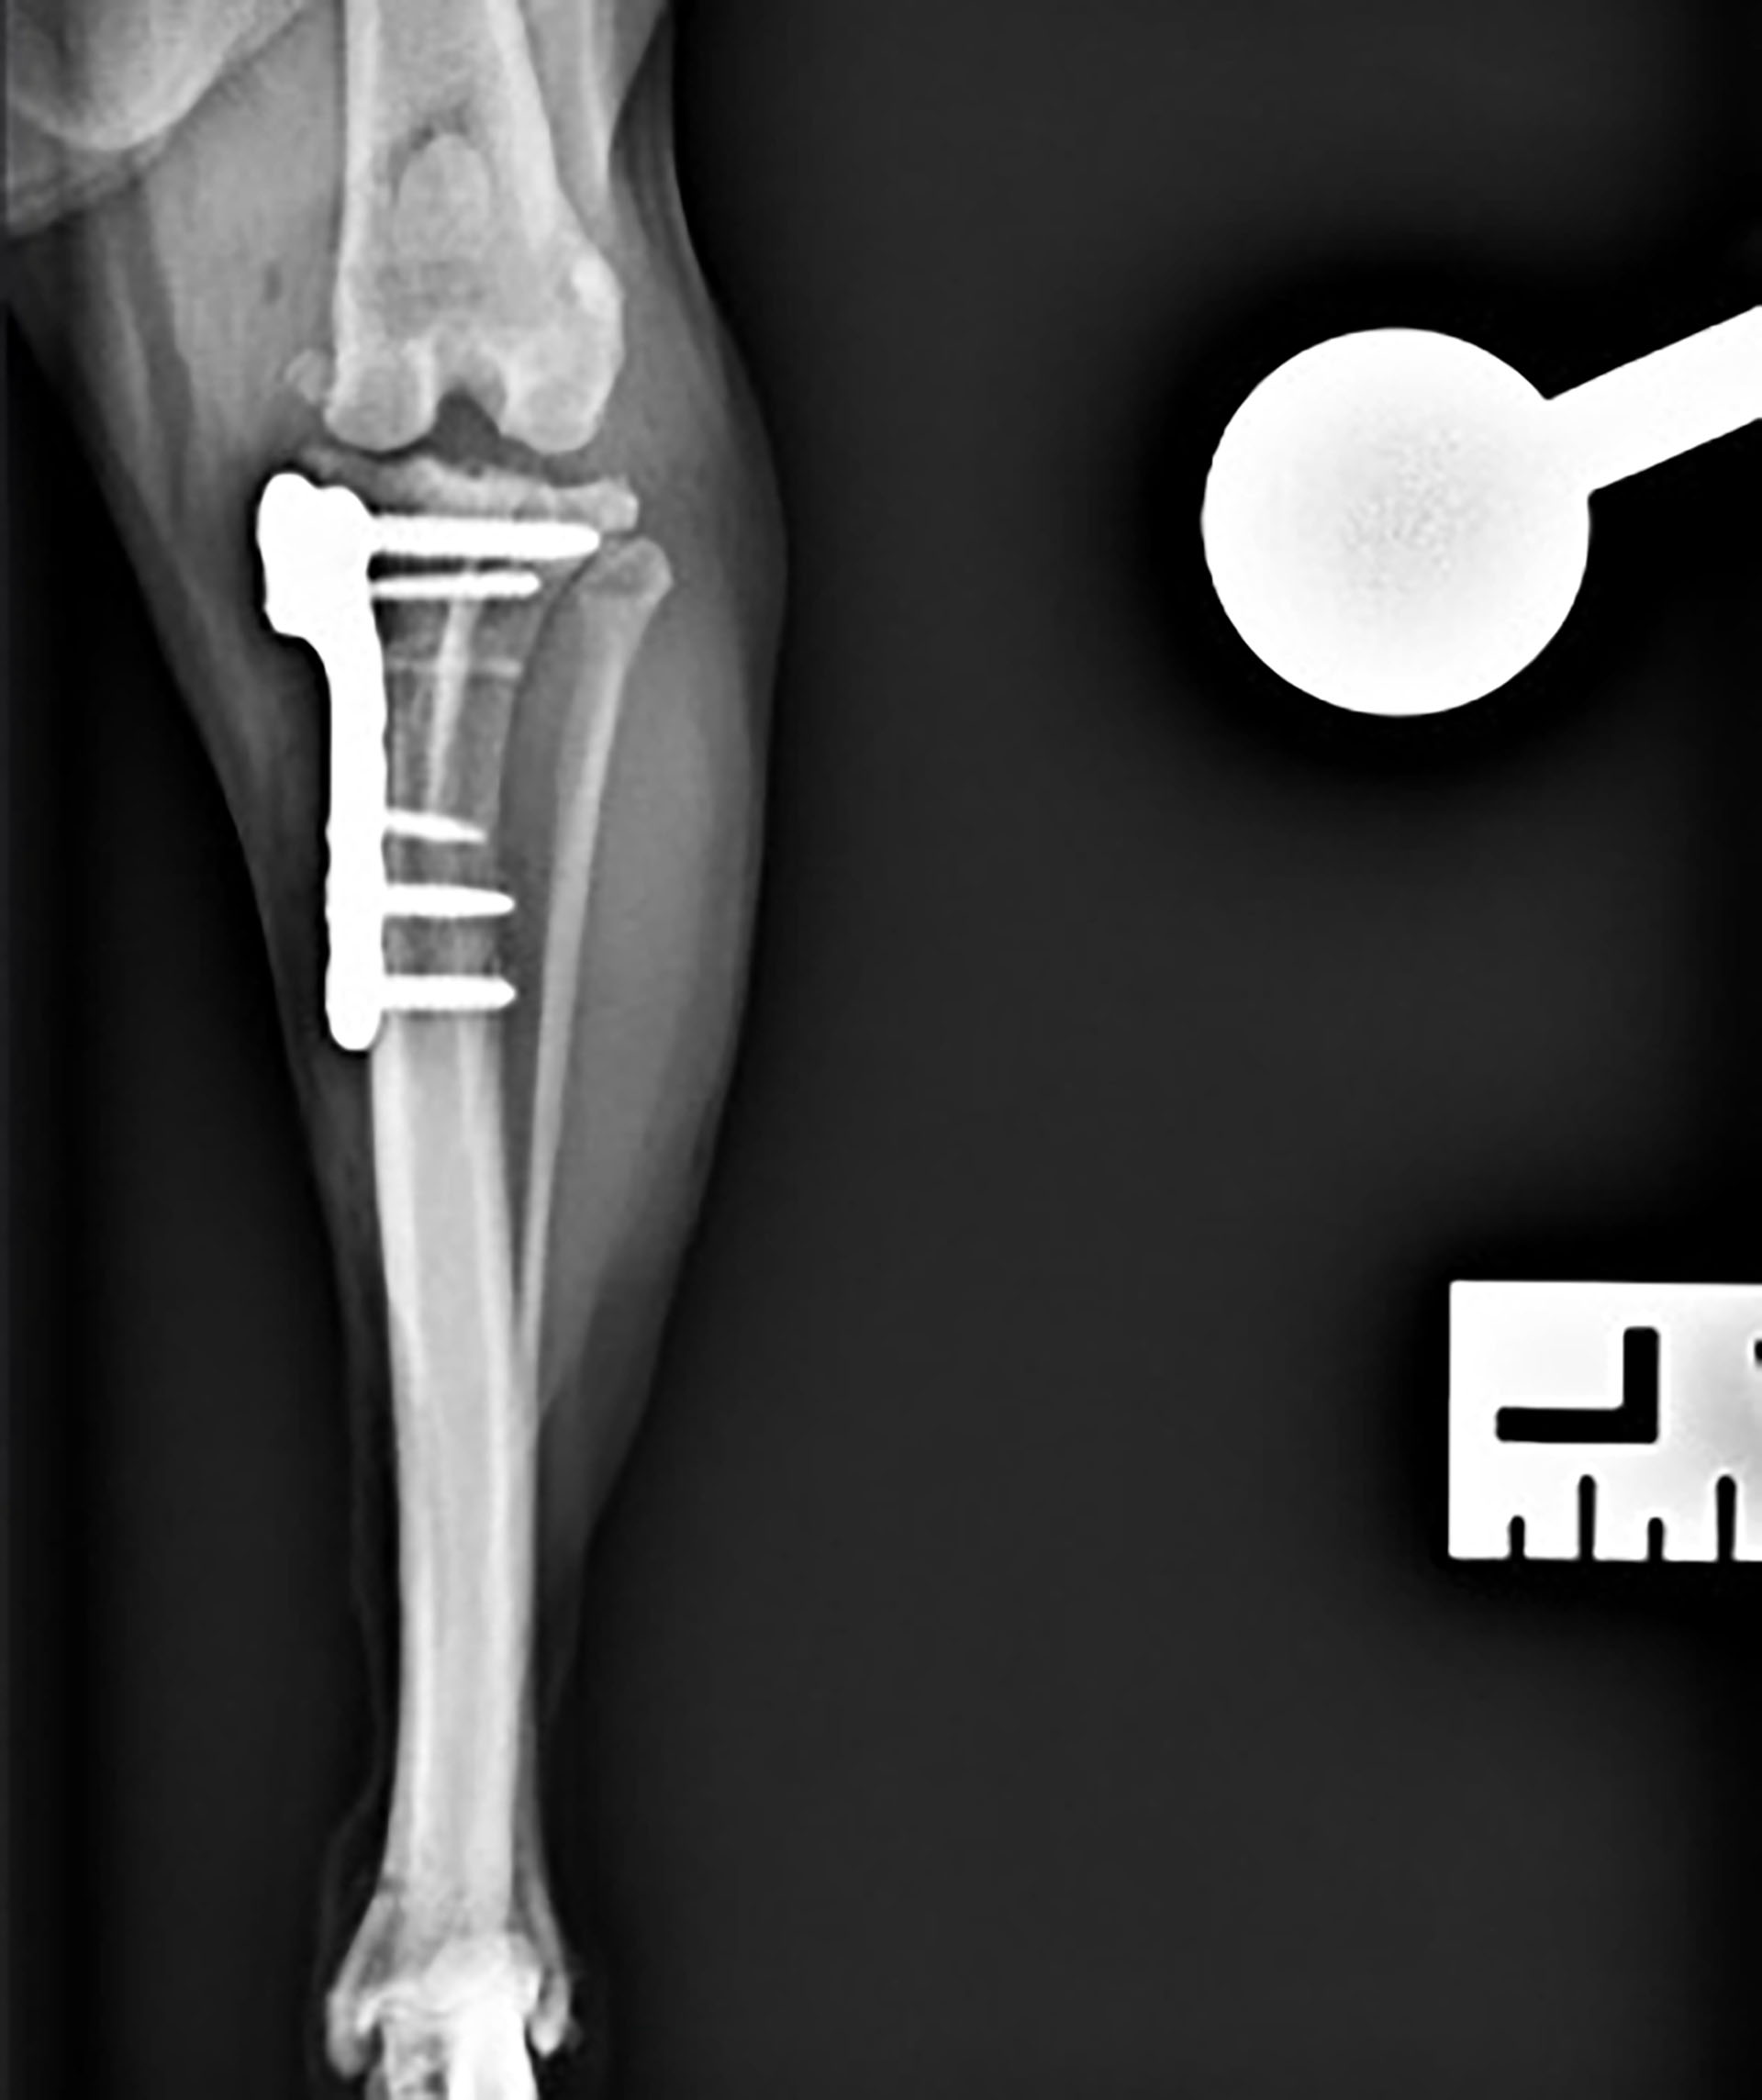

Røntgen (vedlegg 1 – 4):

Figur 1. Laterolateral projeksjon av venstre kne og haseledd. I venstre kneledd var det tydelig effusjon (rød pil), og osteofyttdannelse på patellas apex og femoral ridge (gule piler).

Figur 3 og 4. Kraniokaudal projeksjon av venstre og høyre kneledd og haseledd. I venstre kneledd var det tegn på effusjon (pil).

Laterolateral projeksjon og kraniokaudal projeksjon av hundens høyre og venstre kneledd, tibia, fibula og tarsalledd var tilgjengelig for vurdering. Kvaliteten på bildene var akseptabel. Det ble funnet tydelig effusjon i venstre kneledd med et brattere tibiaplatå enn ved høyre kne. Venstre kne hadde tegn på osteofyttdannelse på apex patella og femoral ridge som tydet på tidlig osteoartoseforandringer. Tibiaplatå vinkelen (TPA) ble målt til 26,2 grader. Denne vinkelen måles mellom en perpendikulær linje til lengdeaksen av tibia og en linje parallell til tibiaplatået. En større tibiaplatåvinkel resulterer i større kranial kraft av tibia under vektbæring. Det kunne ikke påvises annen patologi utifra disse bildene.